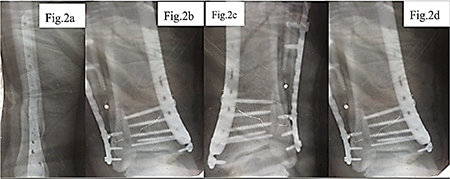

Considering the nature of the fracture and the need for stable fixation of the fragments, a decision was made to perform open osteosynthesis using metal plates, as shown in Figure 2. The surgical treatment was delayed for two weeks due to implant supply interruptions associated with the military conflict in Ukraine. During the operation, two metal plates with a total of 16 screws were implanted, the wound was closed in layers, and four drains were placed to control postoperative fluid outflow.

a – Anteroposterior view of the tibia following osteosynthesis with two metal plates; b – Lateral projection showing fixation with 16 screws securing the plates.; c – Follow-up lateral X-ray demonstrating correct positioning of implants; d – Control X-ray confirming stability of the osteosynthesis construct